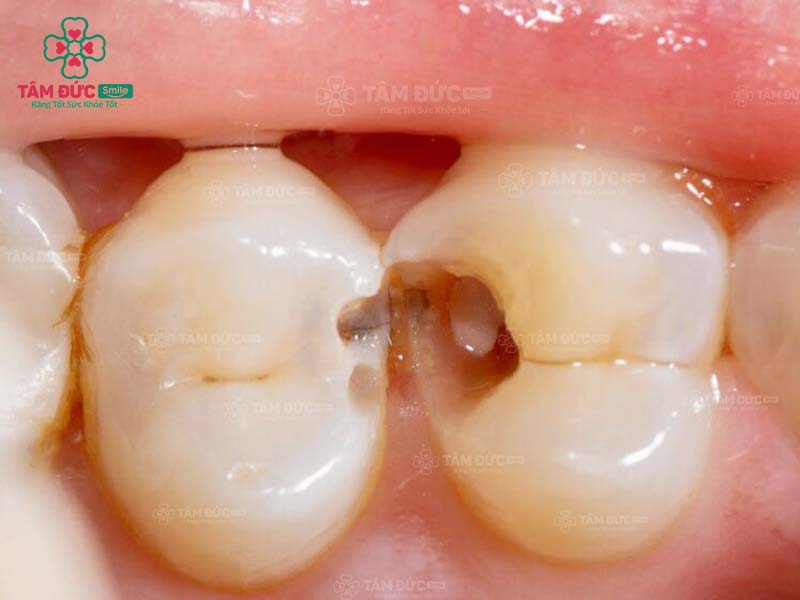

15. Trám răng có cần phải diệt tủy răng hay không?

Trám răng cần diệt tủy răng chỉ áp dụng đối với các trường hợp phải điều trị tủy. Nếu tủy của Quý khách bị viêm nhiễm, thì việc diệt tủy trước khi trám răng là rất cần thiết. Bác sĩ sẽ loại bỏ toàn bộ mô tủy đã chết để giúp Quý khách đảm bảo sức khỏe răng miệng.

Nếu Quý khách chỉ trám răng trong trường hợp răng bị sứt mẻ nhẹ hoặc răng thưa thì không cần diệt tủy răng. Vì quy trình trám răng chỉ tác động đến bề mặt răng, ngoài ra tủy răng của Quý khách cũng đang rất khỏe mạnh.

Nếu sâu răng đến tuỷ, bác sĩ buộc phải lấy tuỷ răng trước khi trám